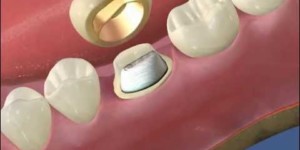

Refacerea dinților

Protetica dentară